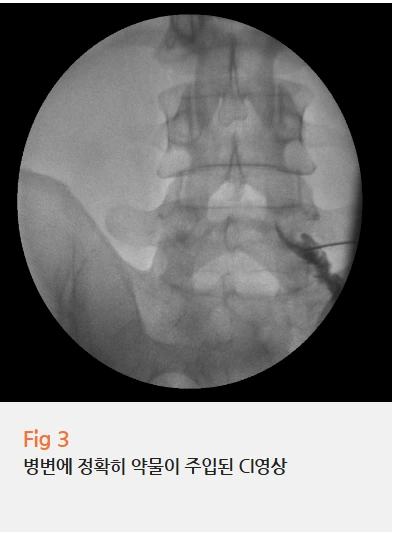

✔️ CI 주사치료는 경막외강 내로 약물을 주입해서 염증을 가라앉히고

신경 압박을 줄여주는 치료예요.

디스크로 인한 신경 자극을 직접적으로 완화시키죠.

%EA%B7%B8%EB%A6%BC7.png?type=w966

[환자분도 C-arm 영상 장비를 통해 병변에 정확히 약을 투여할 수 있었어요. ^^]